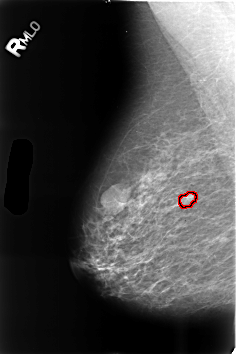

B_3458_1.RIGHT_MLO

RIGHT_MLO LINES 4600 PIXELS_PER_LINE 3056 BITS_PER_PIXEL 12 RESOLUTION 50 OVERLAY

FILE: B_3458_1.RIGHT_MLO.OVERLAY

TOTAL_ABNORMALITIES 1

ABNORMALITY 1

LESION_TYPE MASS SHAPE LOBULATED MARGINS CIRCUMSCRIBED-OBSCURED

ASSESSMENT 4

SUBTLETY 4

PATHOLOGY BENIGN

TOTAL_OUTLINES 1

BOUNDARY